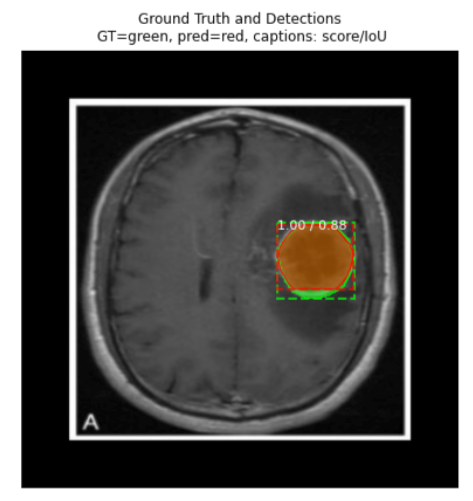

ind = 6

display_image(dataset_val, ind)

predict_and_plot_differences(dataset_val, ind)